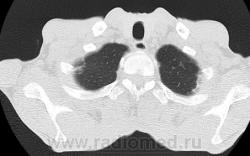

На фоне консолидации полость без содержимого. Может быть всё что угодно, что сопровождается деструкцией. Нужны ещё томограммы в лёгочном окне.

Изображения выставлены все. Ваше мнение уважаемые коллеги?

Это КТ 2-летней давности и попало оно мне в руки, после недавнего прохождения контроля пациентом, когда мы стали перед вопросом о специфическом / не специфическом процессе.

Тогда, пациента 2 месяца лечили от пневмонии, лечили интенсивности, стационарно, в серьёзном учреждении.

Предположу аспергиллез